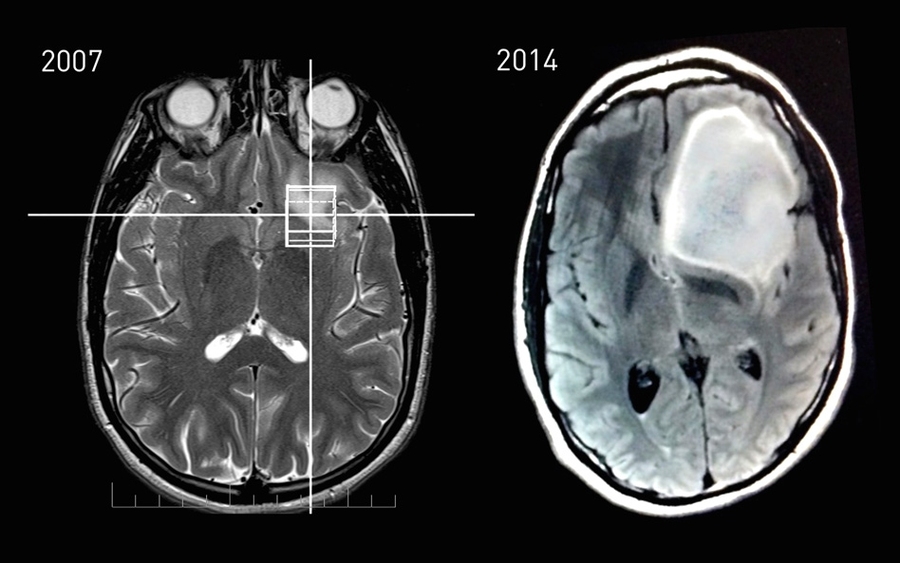

MRI data showing Keating’s astrocytoma tumor growth between 2007 and 2014.

Caption: MRI data showing Keating’s astrocytoma tumor growth between 2007 and 2014.

Credits: Image courtesy of Steven Keating

Image courtesy of Steven Keating